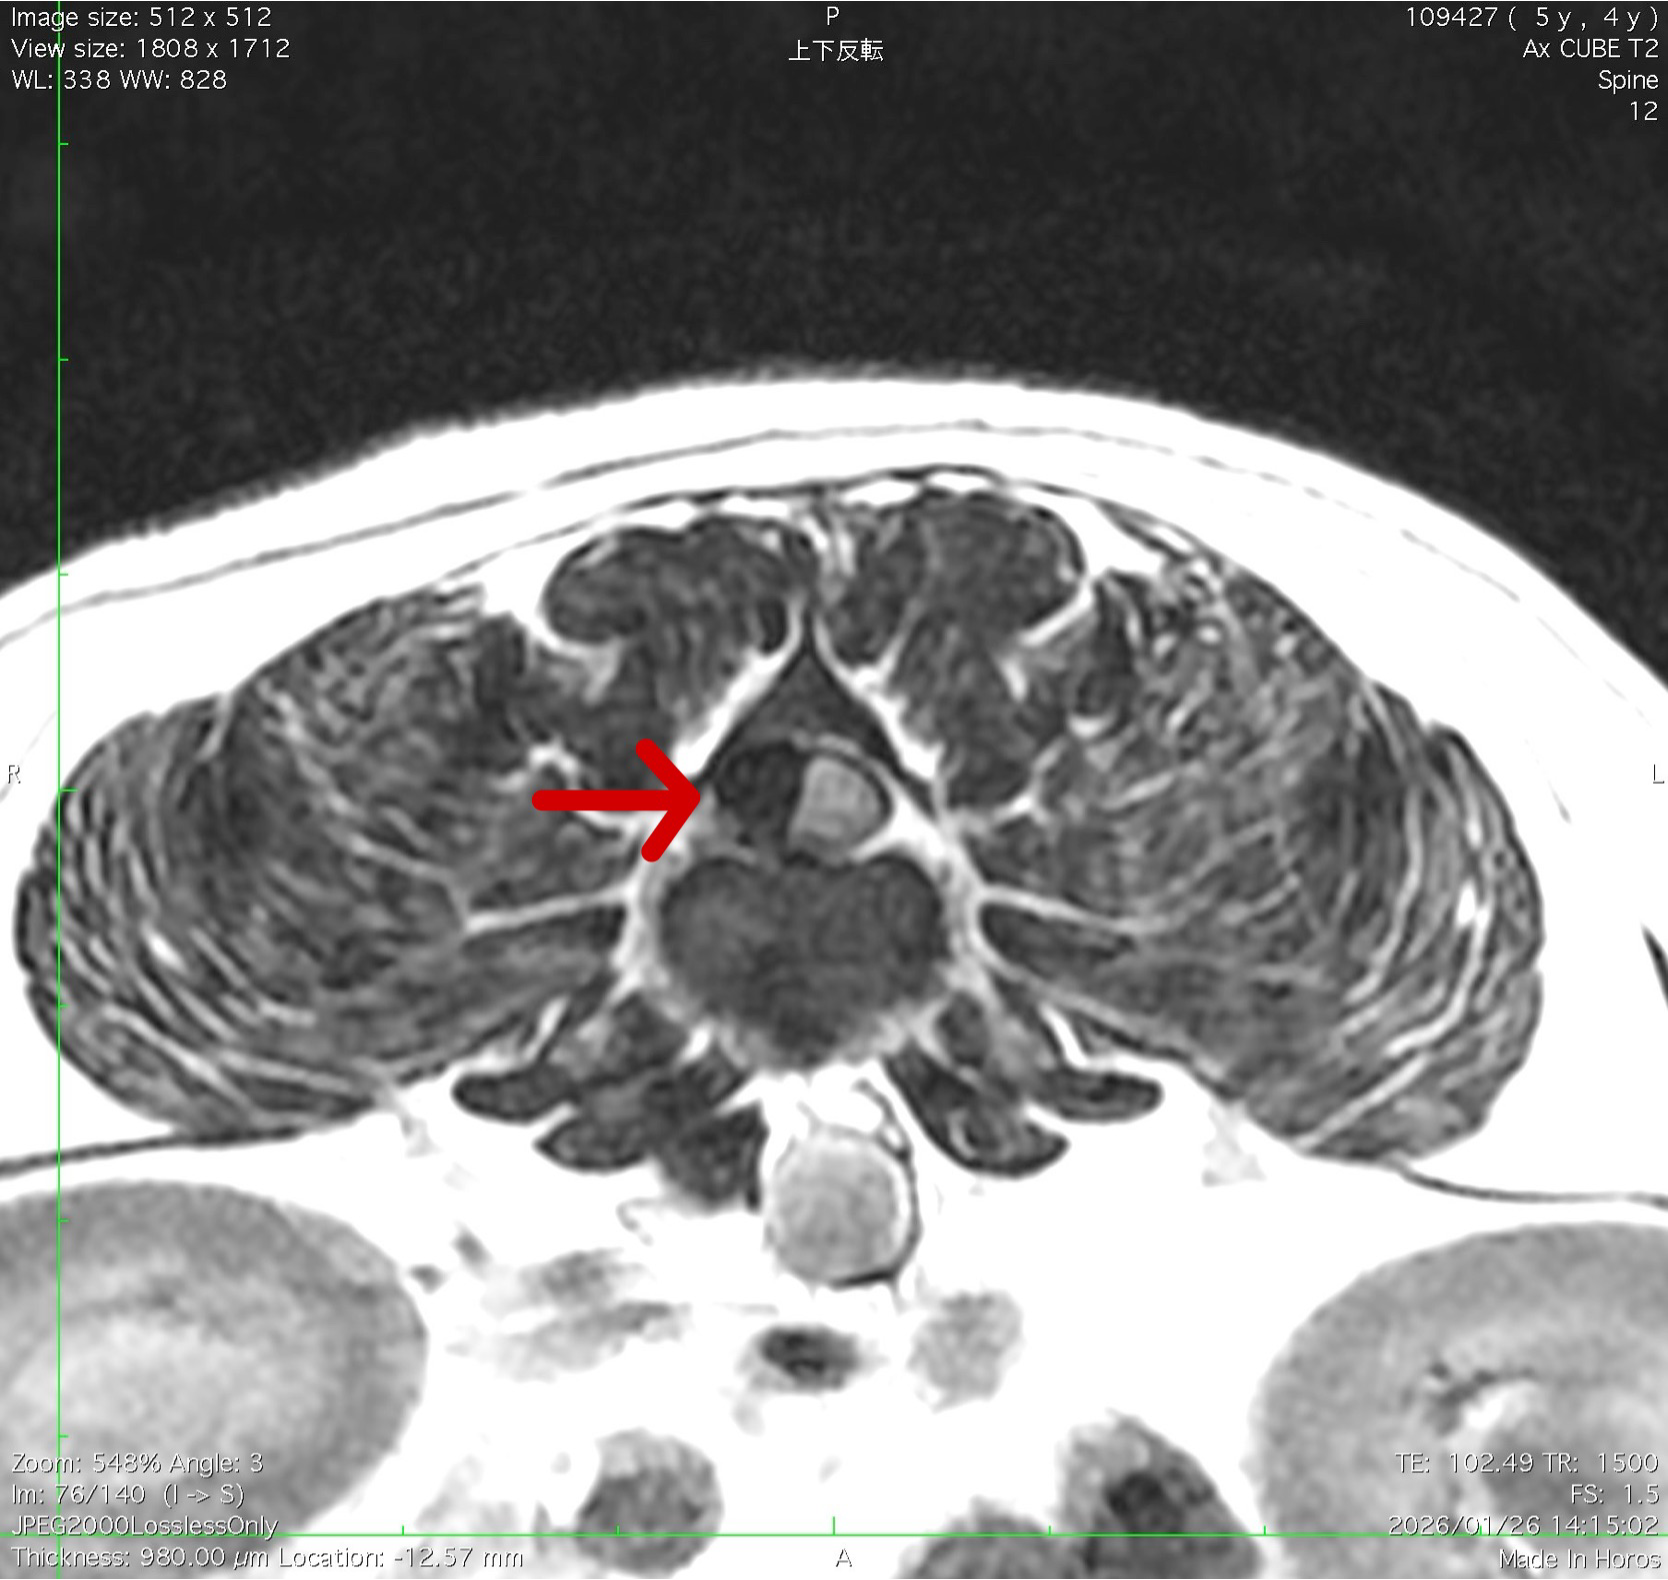

MRI画像 横断面

椎間板が脊髄に右側から圧迫している